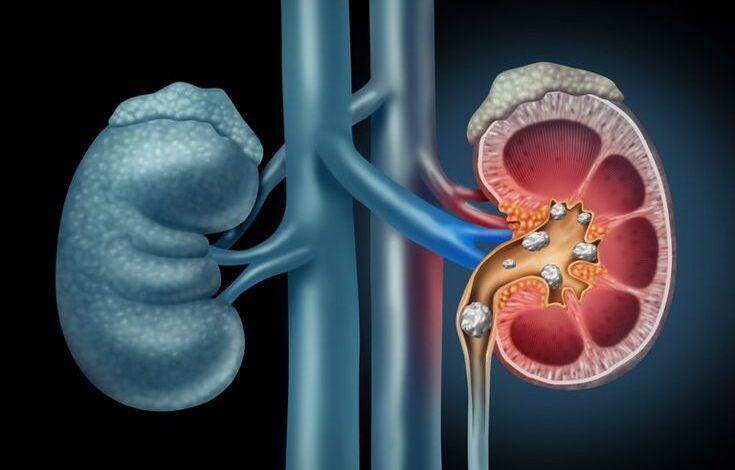

SOLUSIMEDIA.ID — Batu ginjal adalah endapan keras yang terbentuk dari mineral dan garam yang membatu dan mendiami ginjal atau saluran kemih.

Keberadaan batu ginjal dapat memengaruhi kinerja ginjal dalam menyaring darah dan membuang zat sisa melalui urine.

Kondisi ini sering kali dikaitkan dengan kebiasaan kurang minum. Nyatanya, kondisi ini juga disebabkan oleh banyak faktor lain, tidak hanya kurang cairan.

“Batu ginjal tidak hanya disebabkan oleh kurang minum air. Batu terbentuk karena kombinasi faktor metabolik, pola makan, genetik, dan kondisi medis,” ungkap ahli nefrologi Dr Arjun Sabharwal, MBBS dikutip dari Times of India, Selasa (9/12/2025).

“Hal ini telah dibuktikan secara jelas dalam berbagai studi besar yang diterbitkan di The New England Journal of Medicine (NEJM), American Journal of Kidney Diseases (AJKD), dan Nature Reviews Nephrology,” sambungnya.

Adapun berikut ini sederet penyebab paling umum dari batu ginjal:

- Kalsium urine tinggi (hiperkalsiuria).

- Oksalat tinggi (dari makanan atau penyerapan usus).

- Sitrat urine rendah (pelindung alami terhadap batu).

- Asam urat tinggi (sering terkait daging merah & gout).

- Asupan garam dan protein hewani tinggi.

- Asupan kalsium makanan yang rendah.

- Makanan tinggi oksalat (bayam, kacang, cokelat).

- Suplemen vitamin C berlebihan.

- Obesitas, diabetes, gout, gangguan tiroid dan usus.

- Infeksi saluran kemih berulang.

- Riwayat keluarga & faktor genetik.

- Beberapa obat jangka panjang (diuretik, obat migrain, antasida kalsium).

Oleh karena itu, jika masalah ginjal muncul berulang meski sudah minum cukup, pemeriksaan lanjutan perlu dilakukan. Ini bertujuan untuk mengetahui penyebab pasti kemunculan batu ginjal.